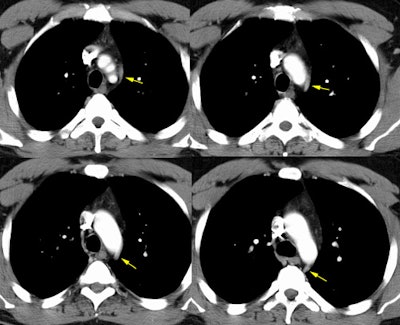

Cross sectional imaging with CT nicely demonstrates the superior intercostal vein and the accessory hemiazygous vein uniting to form a venous arch which courses about the aortic arch (yellow arrows below) to empty into the left brachiocephalic vein (connection not shown on these images), this venous arch is what forms the aortic nipple (click image to enlarge).